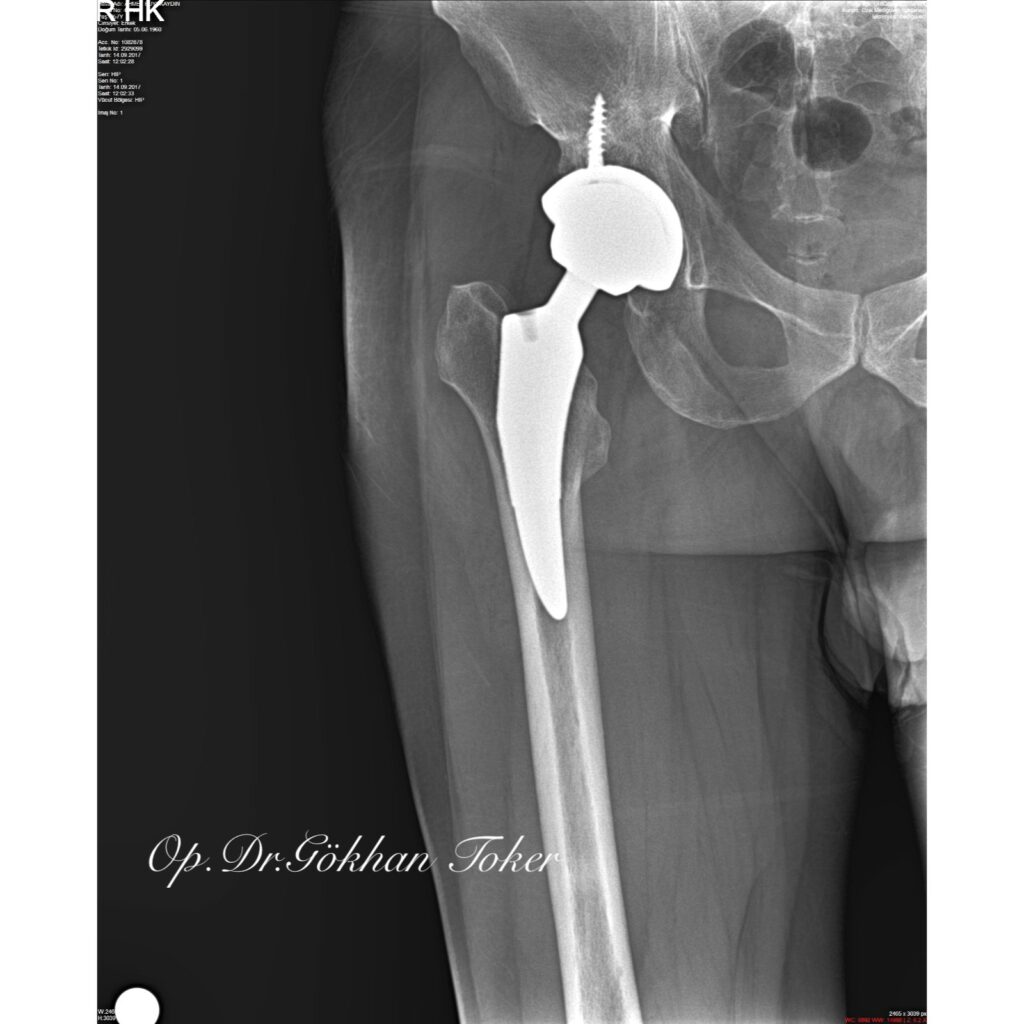

A.B.